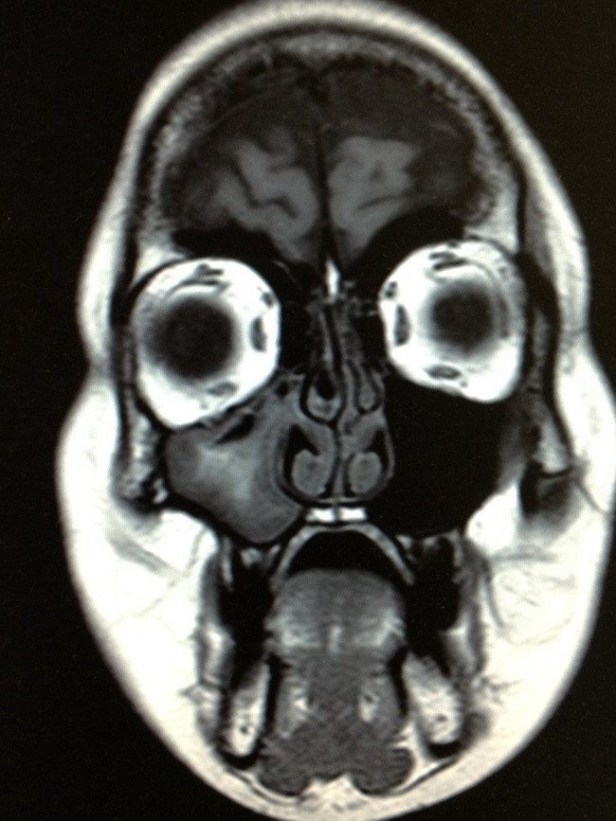

“The mind can play tricks on us,” Lyndon said, bringing us back on the topic of ghosts. “For instance, when I’m having an MRI, sitting in one of those tubes, I am convinced I hear voices.”

“What do you mean you hear voices?” I ask.

“Words, actual words. Usually a repetitive word. It’s very loud in those machines. Have you ever been in one?”

“No I haven’t. How long does it go on for?”

“Oh, you’re in there for a while. On average maybe forty five minutes.”

“A cat scan is different. A cat scan uses X-rays to produce cross-sectional images of the inside of your body, while the MRI uses a magnetic field and radio waves to produce these images. Both of these technologies revolutionized the medical industry when they were introduced in the ‘70’s. Before that, the only way you knew what was going on inside of your body was if they cut you open.”

“That’s an odd coincidence,” I said. “Just the other day I came across a post on Reddit which asked ‘Is the MRI a portal to another dimension?’ It also noted that some people encounter ghosts in the MRI machine.”

“Well, I don’t know if it’s a portal,” Lyndon said, “but it’s sure cramped in there. Some people liken it to a coffin. It’s very constricting. It doesn’t bother me but, if you’re claustrophobic, you’re not going to like it.”